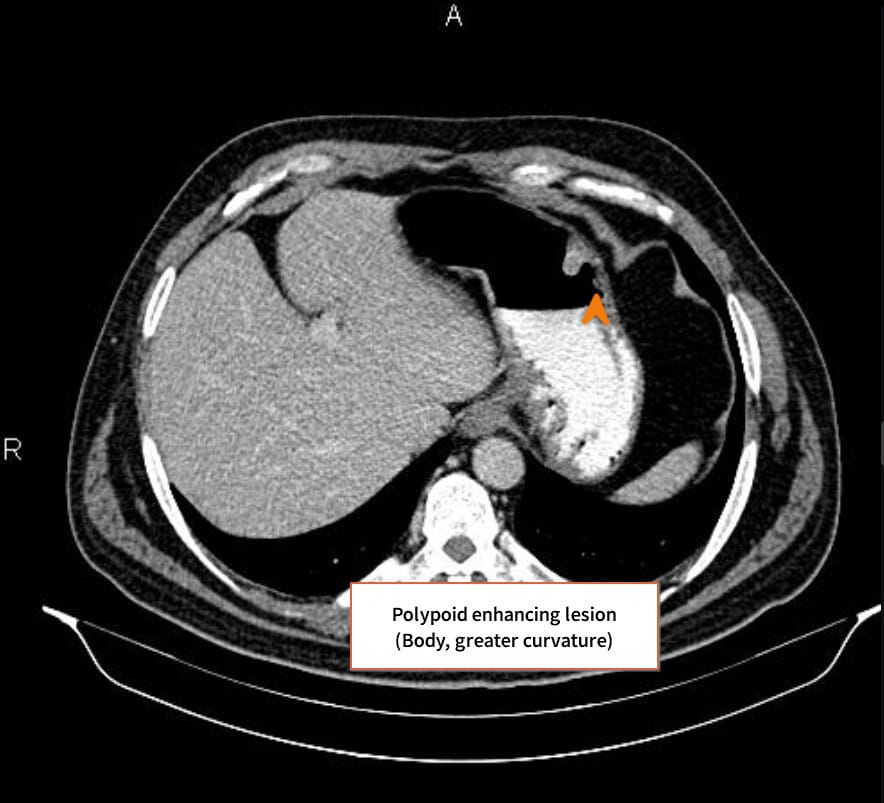

🔵 복부 CT

위벽 비후, 림프절 종대, 인접 장기 침윤, 간 등으로의 전이 확인

Stomach Cancer – 영상 소견상 특징

• Wall thickening and irregular enhancing mass in the gastric antrum region. (Portal venous phase / Delayed Phase)

Niknejad M, Gastric carcinoid tumor. Case study, Radiopaedia.org (Accessed on 14 Jul 2025) https://doi.org/10.53347/rID-201554

Gaillard F, Gastric adenocarcinoma. Case study, Radiopaedia.org (Accessed on 14 Jul 2025) https://doi.org/10.53347/rID-15047

Cuete D, Gastric carcinoma.

Case study, Radiopaedia.org (Accessed on 14 Jul 2025) https://doi.org/10.53347/rID-30234